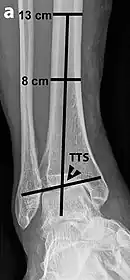

.jpg)

Varus or valgus deformity, if suspected, can be measured with the frontal tibiotalar surface angle (TTS), formed by the mid-longitudinal tibial axis (such as through a line bisecting the tibia at 8 and 13 cm above the tibial plafond) and the talar surface.[24] An angle of less than 84 degrees is regarded as talipes varus, and an angle of more than 94 degrees is regarded as talipes valgus.[25]